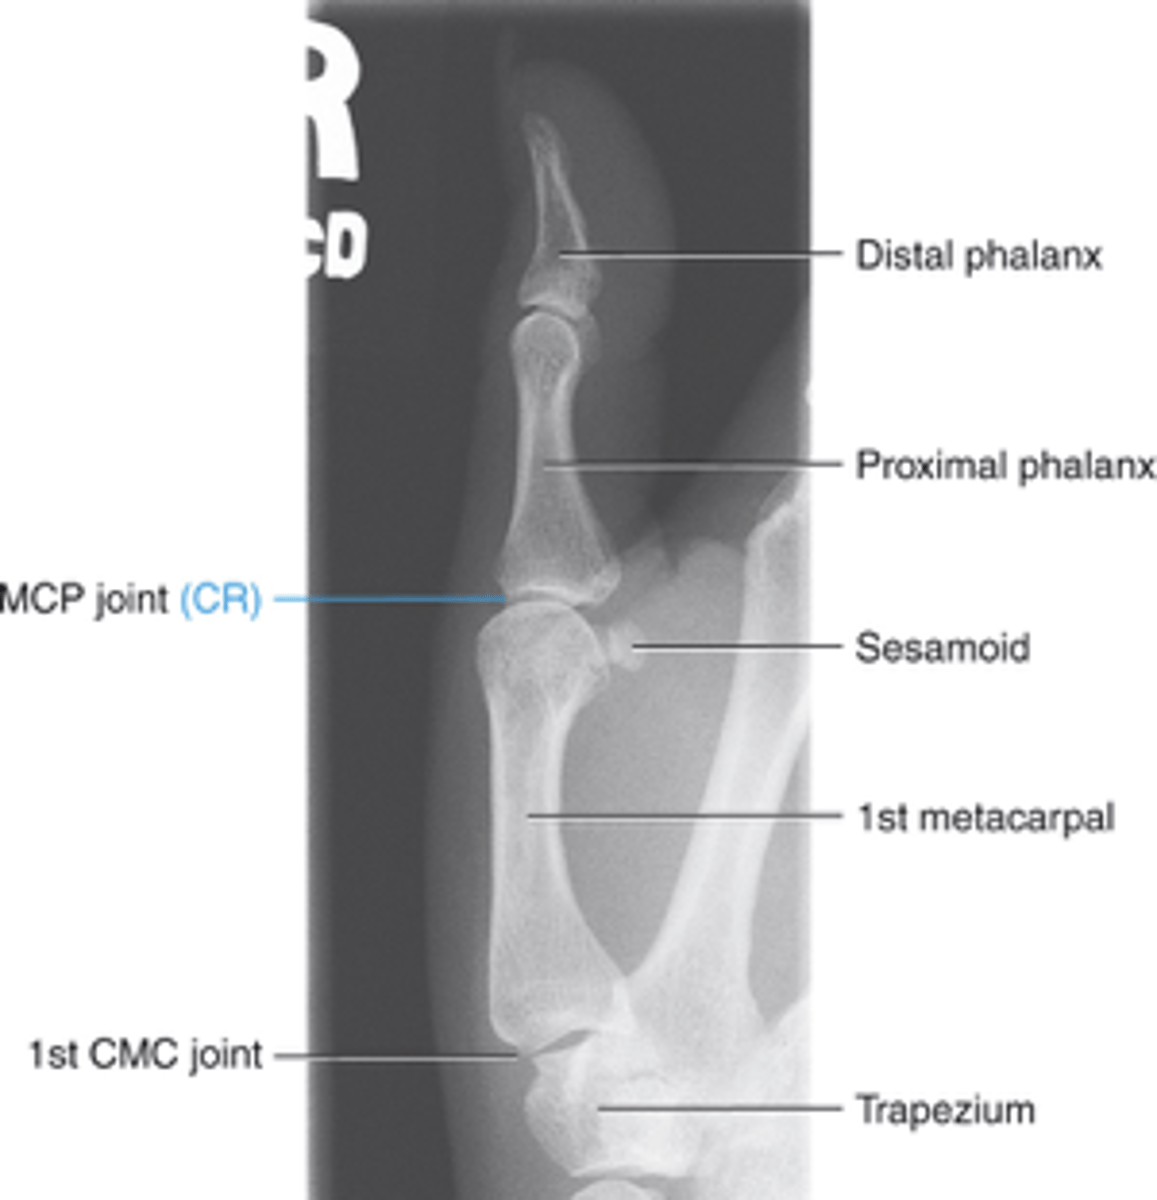

AP thumb